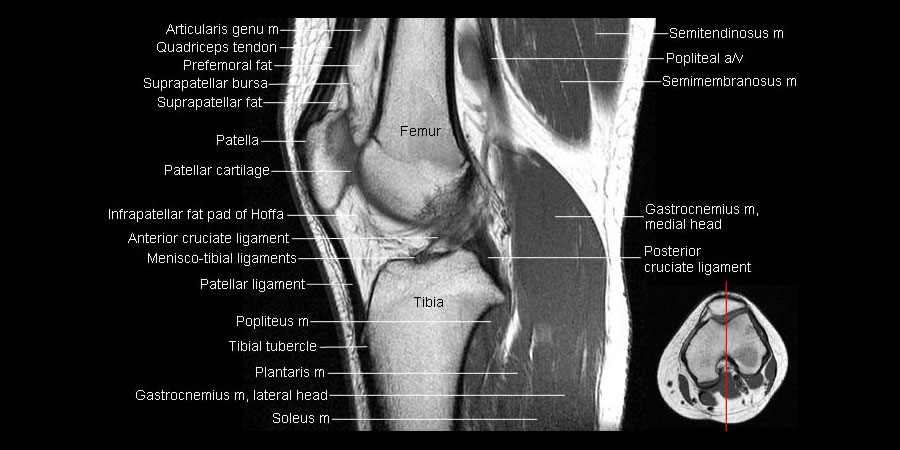

radiographic appearance description

attenuation

radiographs: radiolucent, semi-radiopaque, radiopaque

MRI: void, intermediate signal intensity, high signal intensitiy

ultrasound: anechoic (black), hypoechoic, hyperechoic (bright)